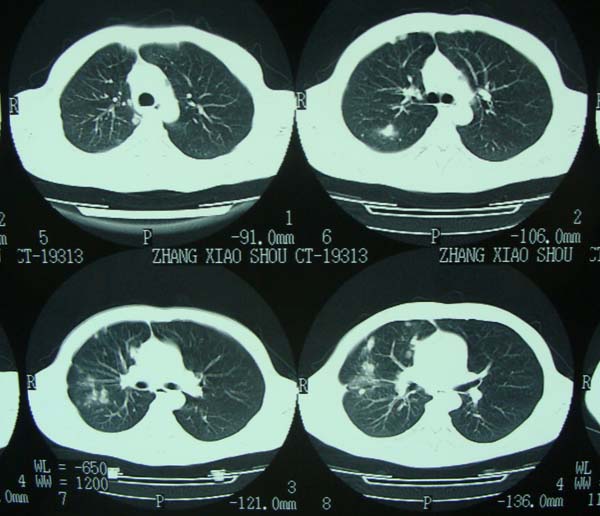

标题: CT15132:男,26岁。建筑混凝土工人。发热。咳。 [打印本页]

标题: CT15132:男,26岁。建筑混凝土工人。发热。咳。

右肺继发型肺结核,右侧胸腔积液、胸膜肥厚粘连。

右肺多发园形结节考虑不考虑转移?

首先考虑结核结节(建议结合实验室检查明确)。转移瘤不能完全除外。

年轻男性,右肺多形性病灶伴右侧胸腔积液,考虑结核

右肺及胸胸膜多个结节多考虑转移瘤,右侧胸水,结核次之。